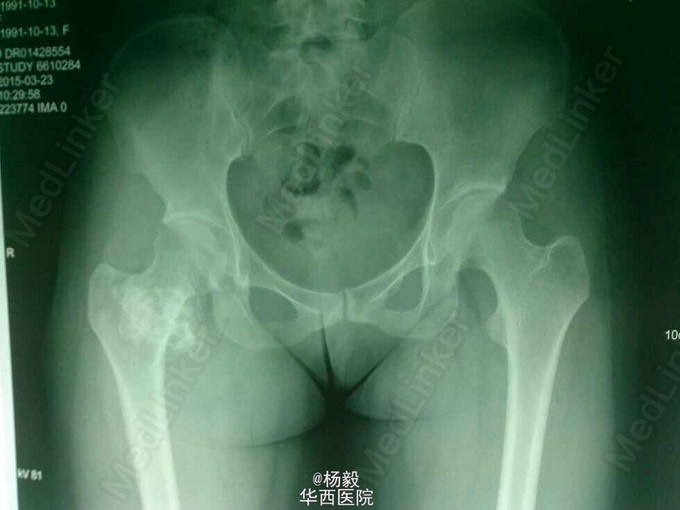

今日门诊病例分享:右股骨转子区骨软骨瘤

患者以发现右臀部股骨区巨大包块伴随疼痛活动障碍4年就诊。体检发现右臀部转子区20*20*10cm巨大包块,坚硬,四肢肌力正常,深浅发射正常。暂无抽血报告。x线如图所示,7*7cm大小包块,显示比体检大小小很多,说明有软骨帽,不显影。诊断为:右股骨转子区骨软骨瘤。建议入院手术。总结:此处应及早手术,因引起患者疼痛,活动受限,还有可能引起病理性骨折,恶变等。建议手术。